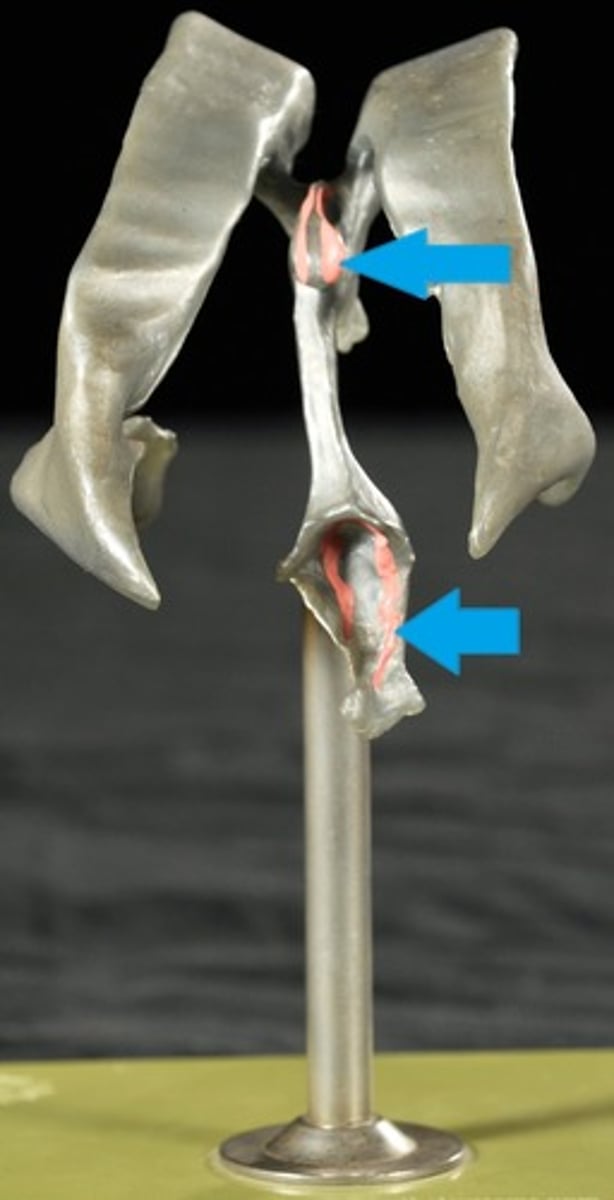

Ventricles

1) Right & left lateral ventricles:

-Anterior, Posterior & inferior horns

2) 3rd Ventricle, Cerebral aqueduct, 4th ventricles

4) Apertures (Narrow openings) into subarachnoid space of spinal cord

Anterior Horns

Posterior Horns

Inferior Horns

3rd Ventricle

4th Ventricle